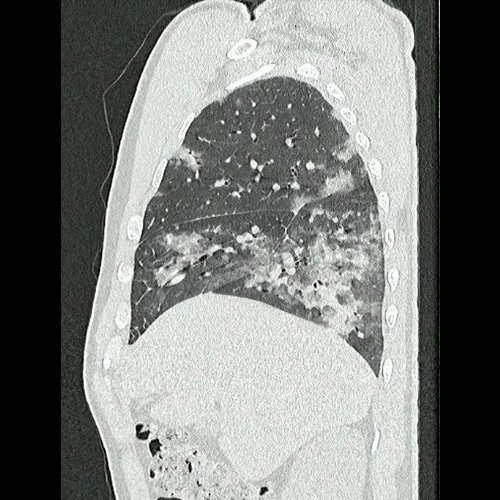

• Tomografía de tórax sin contraste endovenoso (Dia 0):Se observan múltiples áreas de consolidación parenquimatosa con broncograma aéreo y de distribución difusa por ambos pulmones, predominando en los lóbulos inferiores, asociadas a engrosamiento de los septos y rodeadas de tenue vidrio esmerilado. Se identifican estructuras ganglionares lateroaórticas, pretraqueales y subcarinales, ninguna de ellas sin alcanzar rango megálico.

Tomografía de tórax sin contraste endovenosos (Ventana pulmonar- corte sagital)